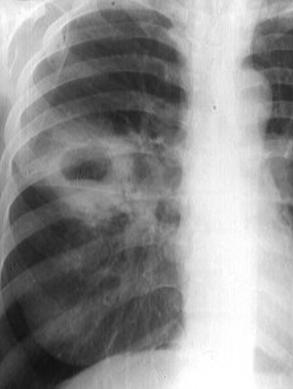

Rx toracică, incidență P-A

DESCRIERE:

pe tot teritoriul pulmonar, bilateral → opacități nodulare multiple de dimensiuni variabile, intensitate medie-mare, omogene, cu contur imprecis delim

confluente

distribuție anarhică

DX: bronhopneumonie

DD:

miliara TBC

MTS pulm hematogene